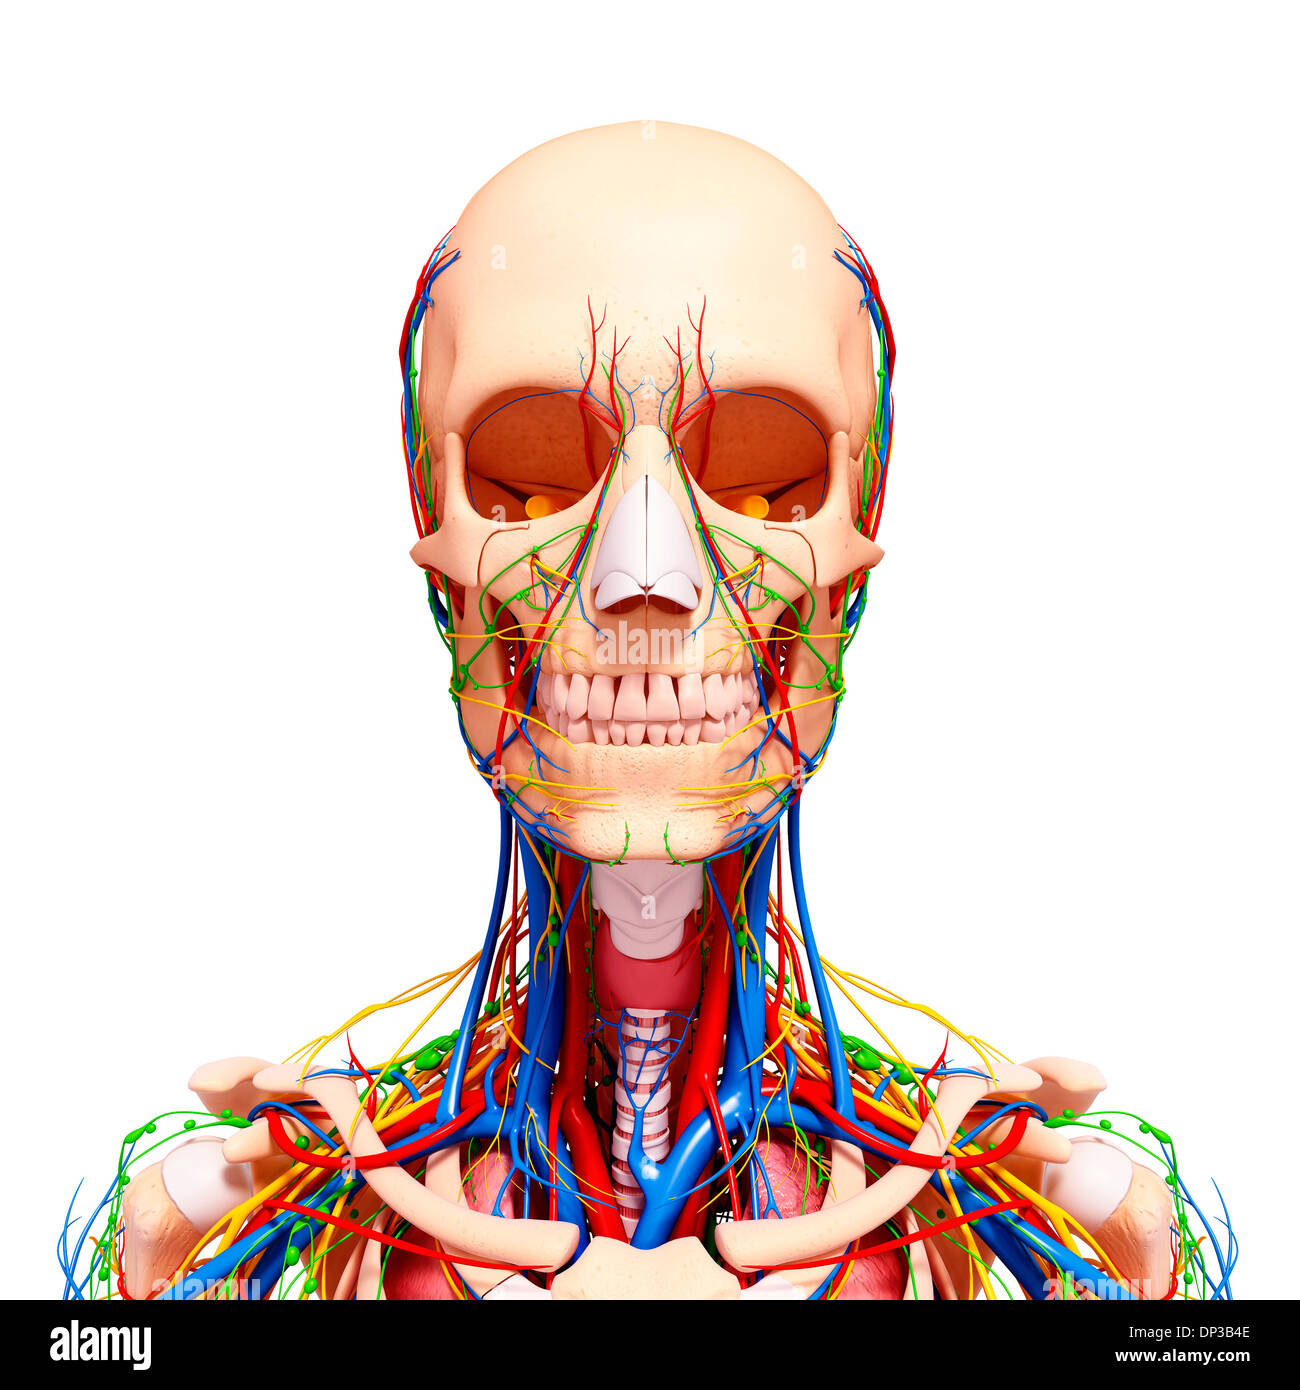

female anatomy art Complete female anatomy 3d model

fineartamerica.comFemale Anatomy, Artwork Stock Photo - Alamy

fineartamerica.comFemale Anatomy, Artwork Stock Photo - Alamy

fineartamerica.comFemale Anatomy, Artwork Stock Photo - Alamy

fineartamerica.comFemale Anatomy, Artwork Stock Photo - Alamy

www.alamy.comFemale Anatomy, Artwork Stock Photo - Alamy

www.alamy.comFemale Anatomy, Artwork Stock Photo - Alamy

bocadowasubo.github.ioFemale Anatomy, Artwork Stock Photo - Alamy

bocadowasubo.github.ioFemale Anatomy, Artwork Stock Photo - Alamy

fineartamerica.comFemale Anatomy, Artwork Stock Photo - Alamy

fineartamerica.comFemale Anatomy, Artwork Stock Photo - Alamy

www.etsy.comFemale Anatomy, Artwork Stock Photo - Alamy

www.etsy.comFemale Anatomy, Artwork Stock Photo - Alamy

www.alamy.comFemale Anatomy, Artwork Stock Photo - Alamy

www.alamy.comFemale Anatomy, Artwork Stock Photo - Alamy

www.alamy.comFemale Anatomy, Artwork Stock Photo - Alamy

www.alamy.comFemale Anatomy, Artwork Stock Photo - Alamy

fineartamerica.comFemale Anatomy, Artwork Stock Photo - Alamy

fineartamerica.comFemale Anatomy, Artwork Stock Photo - Alamy

Female Anatomy, Artwork Stock Photo - Alamy

www.alamy.comFemale Anatomy, Artwork Stock Photo - Alamy

www.alamy.comFemale Anatomy, Artwork Stock Photo - Alamy

www.etsy.comFemale Anatomy, Artwork Stock Photo - Alamy

www.etsy.comFemale Anatomy, Artwork Stock Photo - Alamy

www.alamy.comFemale Anatomy, Artwork Stock Photo - Alamy

www.alamy.comFemale Anatomy, Artwork Stock Photo - Alamy

www.alamy.comFemale Anatomy, Artwork Stock Photo - Alamy

www.alamy.comFemale Anatomy, Artwork Stock Photo - Alamy

Female Anatomy, Artwork Stock Photo - Alamy

www.alamy.com3d Rendered Illustration Of The Female Anatomy Stock Photo - Alamy

www.alamy.com3d Rendered Illustration Of The Female Anatomy Stock Photo - Alamy

fineartamerica.com3d Rendered Illustration Of The Female Anatomy Stock Photo - Alamy

fineartamerica.com3d Rendered Illustration Of The Female Anatomy Stock Photo - Alamy

pixels.comFemale Anatomy, Artwork Stock Photo - Alamy

pixels.comFemale Anatomy, Artwork Stock Photo - Alamy

www.alamy.comFemale anatomy art print women body torso drawing illustration modern. Female anatomy photograph by pixologicstudio/science photo library. Female anatomy, artwork stock photo

www.alamy.comFemale anatomy art print women body torso drawing illustration modern. Female anatomy photograph by pixologicstudio/science photo library. Female anatomy, artwork stock photo